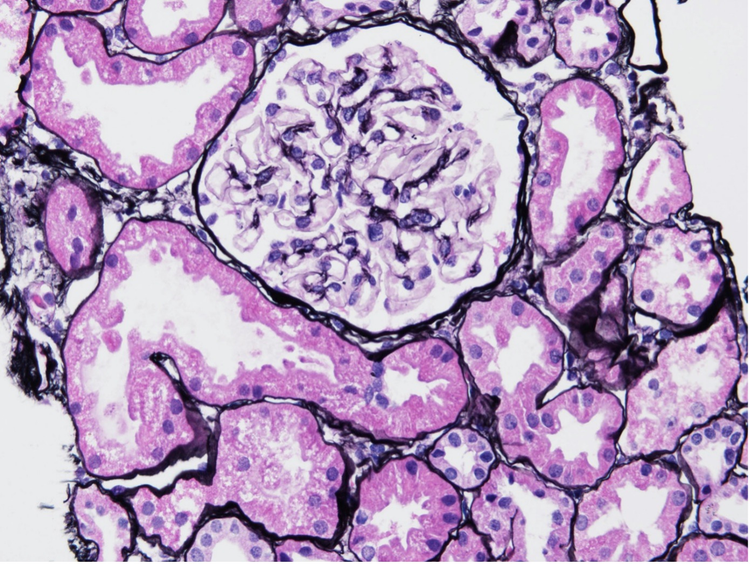

Par exemple, la figure 1 illustre des échantillons rénaux de patients à un stade précoce de NL de classe 1, sans changements glomérulaires significatifs par rapport à des sujets en bonne santé. 2

Figure 1. Échantillon de biopsie de rein atteint de NL de classe 1 coloré avec la coloration argentique de Jones